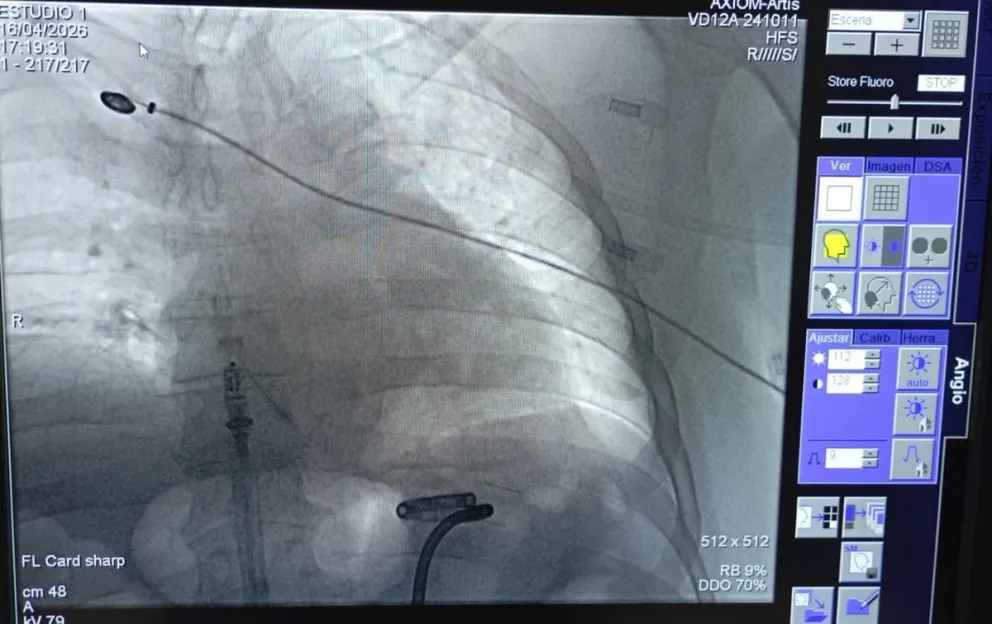

**La Clínica Viedma, en Viedma, fue el primer centro médico de la provincia en implantar el dispositivo Micra AV2 de Medtronic, 10 veces más pequeño que uno convencional. La intervención duró 40 minutos.**

Un paciente de 56 años recibió en la Clínica Viedma el marcapasos más pequeño del mundo, el Micra AV2 de Medtronic. La intervención fue realizada por el equipo del Servicio de Electrofisiología de la Unidad de Cardiología del establecimiento, encabezado por Martín Calvelo, jefe de Cardiología, con la supervisión del médico proctor Ariel Estévez, especializado en este tipo de cirugías.

El paciente presentaba infecciones de catéteres a repetición que impedían la colocación de un marcapasos convencional por la vía tradicional. El dispositivo implantado mide dos centímetros de longitud, pesa dos gramos y es un 93% más pequeño que los modelos tradicionales. Además, tiene una autonomía de entre ocho y 13 años, un 40% más que los convencionales.

"Somos el primer centro médico de Río Negro en adoptar la tecnología Medtronic Micra AV2", afirmó Calvelo. A diferencia de los marcapasos tradicionales, el dispositivo no requiere cables ni bolsillo subcutáneo, lo que elimina el riesgo de infecciones asociadas a esos elementos.

Calvelo explicó a NoticiasNet que el dispositivo se adapta "inmediatamente" al cuerpo del paciente y que este "no tiene restricciones" en su vida cotidiana: "Puede hacer la actividad física que quiera", señaló. La única indicación es avisar en controles de seguridad aeroportuarios que porta el dispositivo.